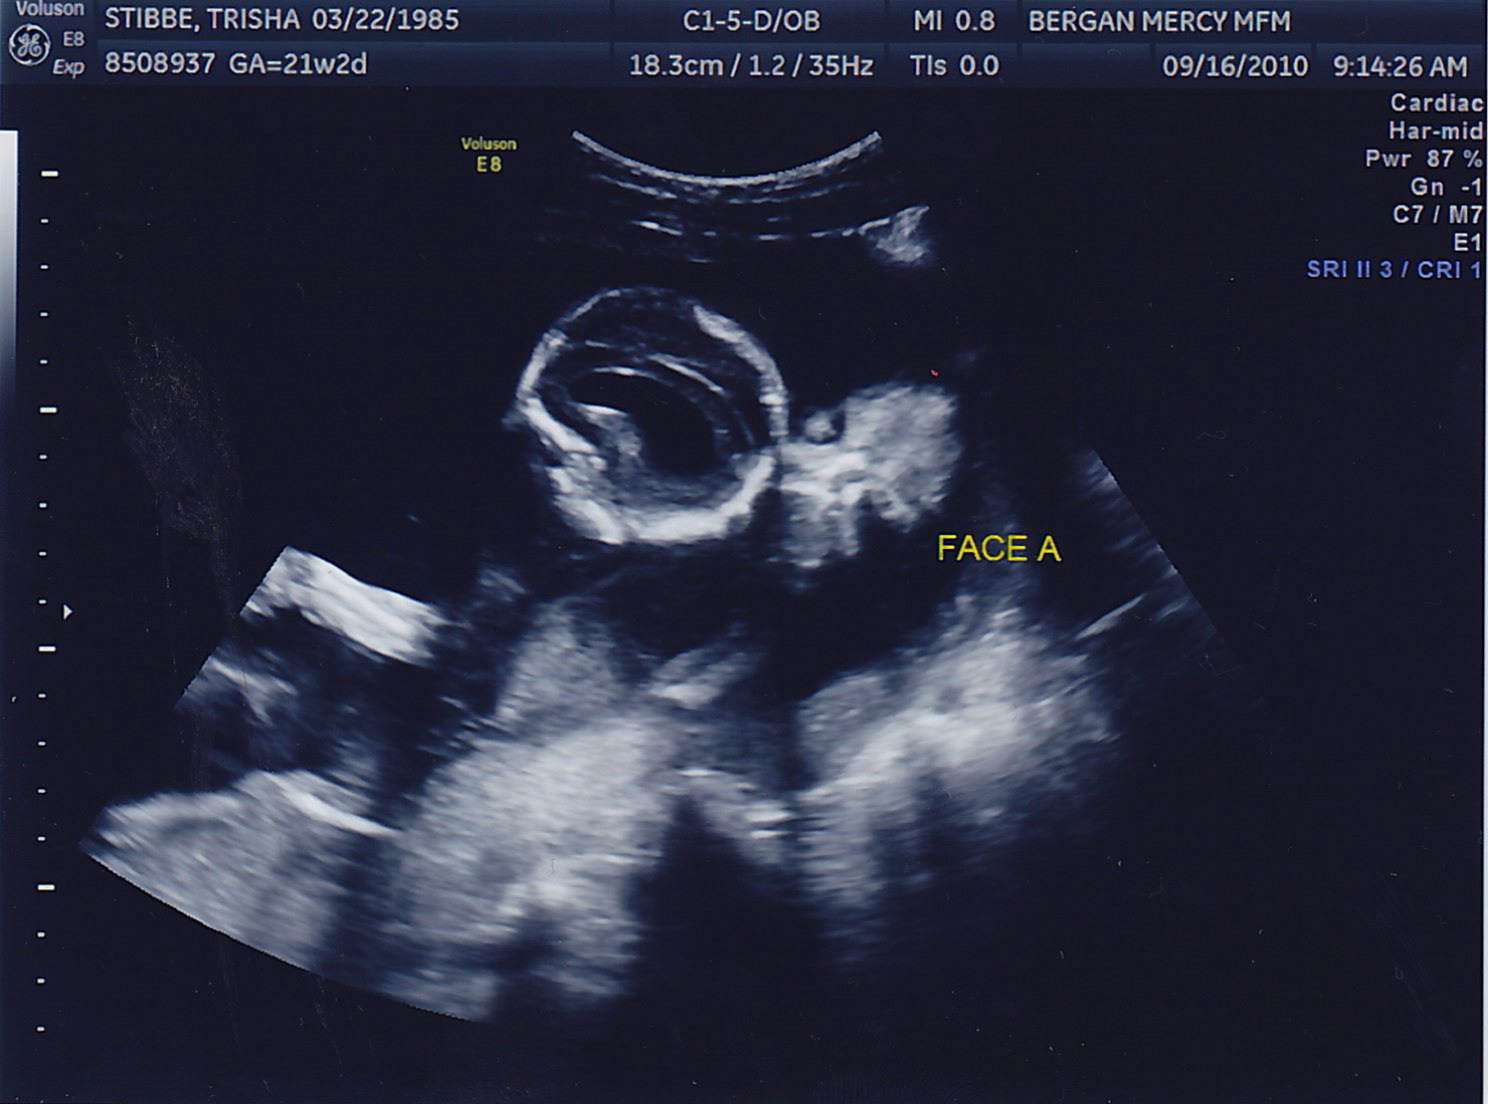

Another successful appointment! Both boys gained weight, we could see the bladder on Baby B (something the doctor needs to keep a close eye on) and the fluid levels in both looked great. No amnio therapy for Mommy today! Here are some more pictures of the little peanuts, who were called “photogenic” by the sonographer today <– very proud Mom-moment 🙂